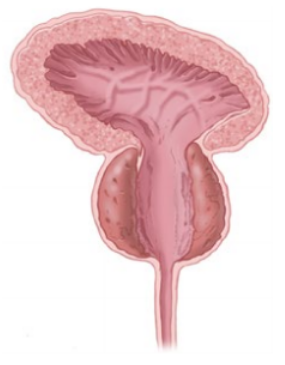

Prostat Görüntüsü

GreenLight operasyonu geçiren kişiler genellikle, ameliyattan birkaç saat içinde evlerine dönebilirler. İşlem sonunda mesanenize bir idrar yerleştirilir ise, tipik olarak 24 saat içinde çıkartılır. Bununla birlikte, bazı durumlarda hastalarda sonda daha uzun süre kalabilir.

Çoğu hasta semptomlarında çok hızlı bir rahatlama ve idrar akışında dramatik bir iyileşme yaşarlar. Bu rahatlama, operasyondan sonraki 24 saat içinde gerçekleşir. Ancak her hastanın denetimi farklı olabilir.